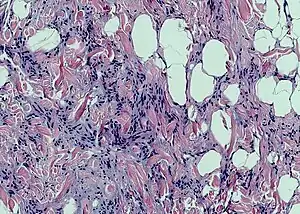

Spindle cell lipoma is an asymptomatic, slow-growing subcutaneous tumor that has a predilection for the posterior back, neck, and shoulders of older men.[1]: 625 [2]

Histopathological examination of spindle cell lipoma